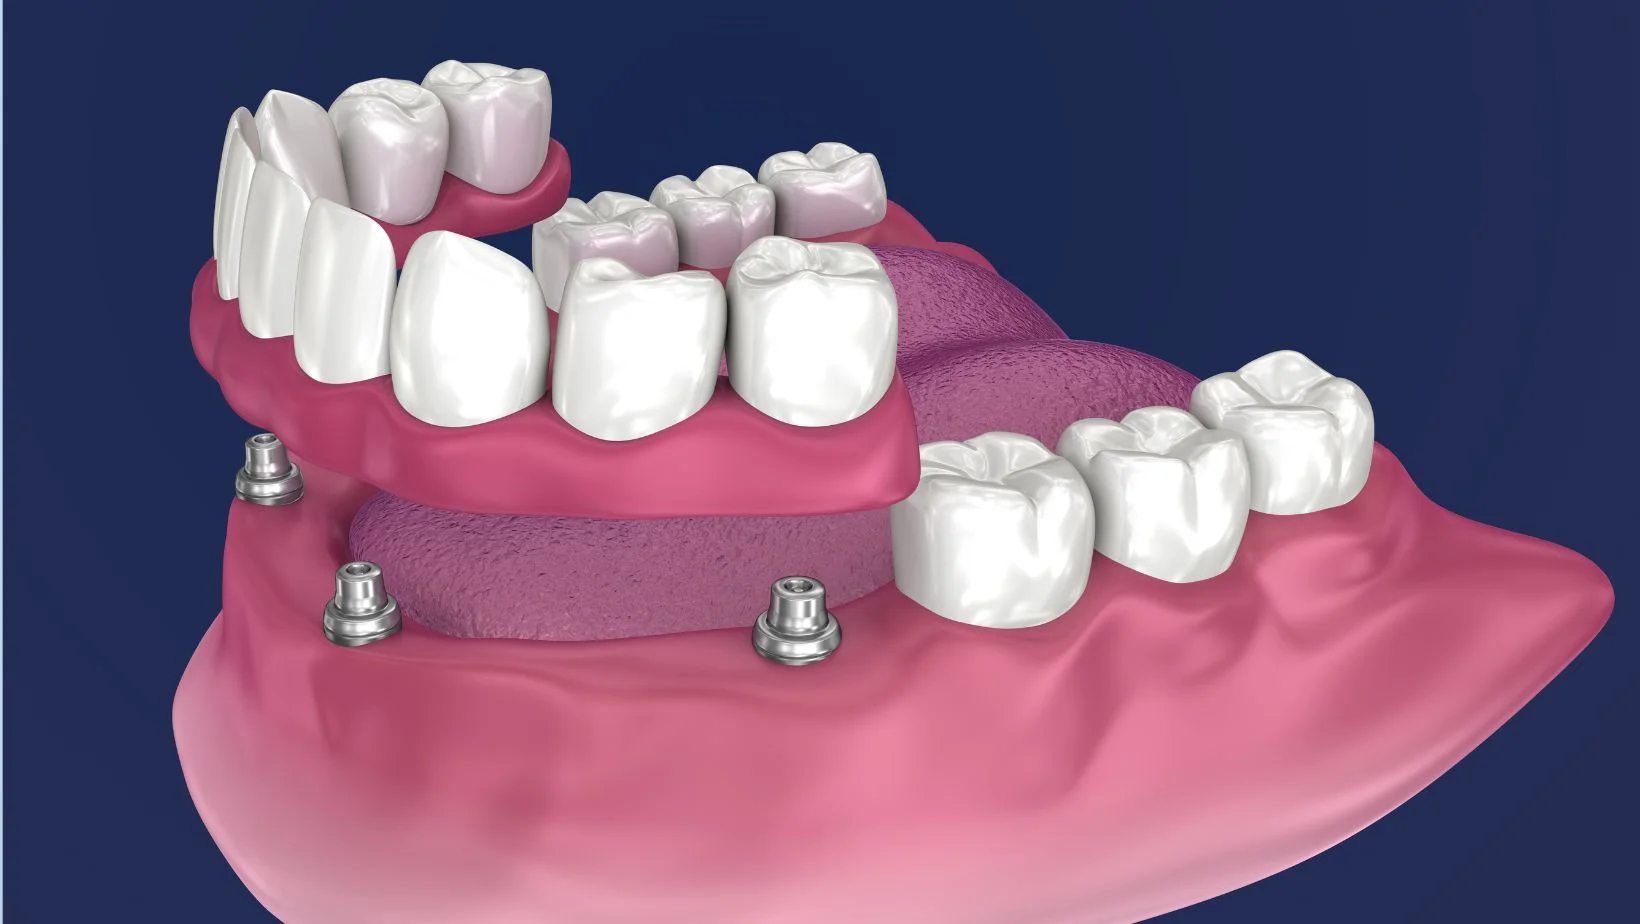

Prótesis removible sobredentadura con anclajes tipo locator

Sobredentadura

Removible con locators (mucha retención, fácil higiene).

Sobredentadura retenida a implantes con anclajes tipo locator

Sobredentadura (locators)

Arcada inferior con alta retención y comodidad, removible para higiene diaria. Gran mejora de estabilidad.